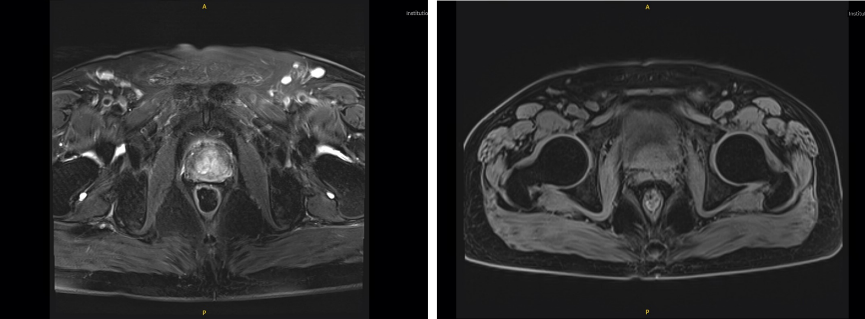

2023年6月9日,复查MRI:

T1WI示前列腺体积未见明显增大,3.3 × 3.2 × 2.5 cm,体积13 mL;T2WI示前列腺中央带及周围带多发结节影较前明显减少、减小,前列腺包膜及假包膜局部显示欠清,与膀胱及精囊分界较前清晰;双侧髂血管旁未见明显增大淋巴结。

图 3 2023年6月9日前列腺癌MRI平扫